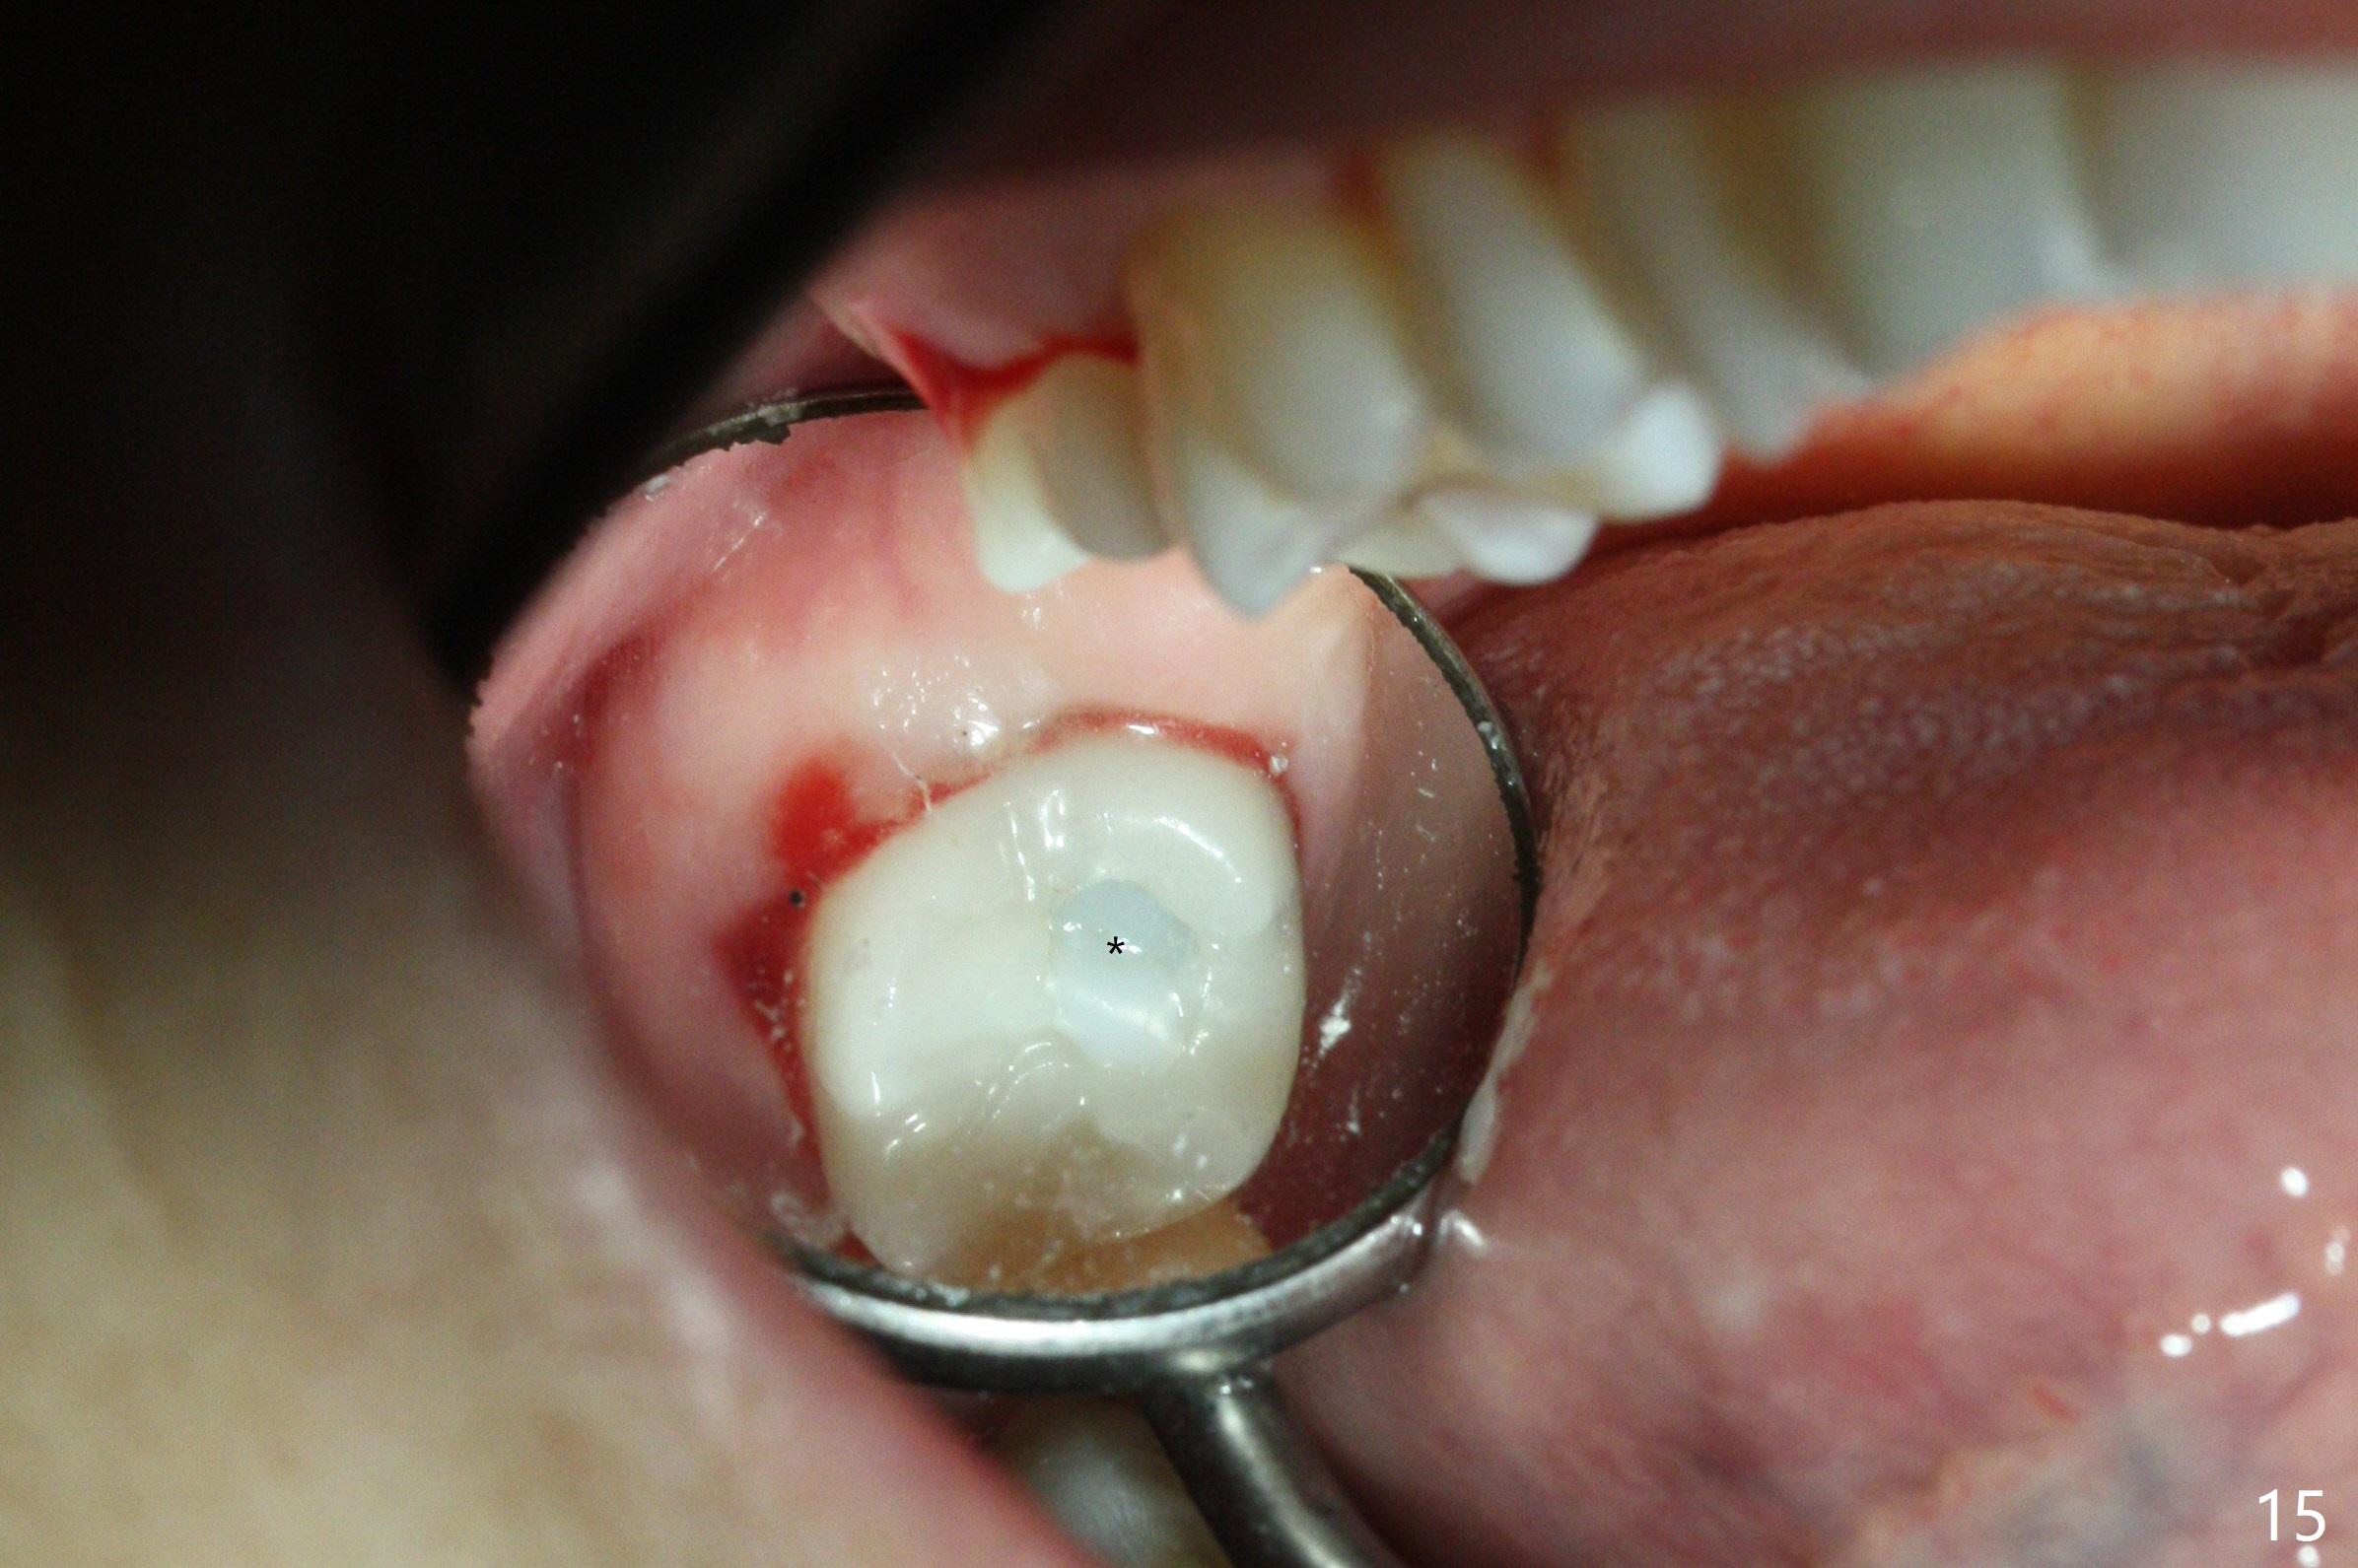

Fig.5 shows the mesial slope of the socket (M), which is more or less the center of the socket mesiodistally. If the osteotomy were set up in the red circle (Fig.6) in the mesial slope (Fig.8 green dashed line), the trajectory of 4.5x11 mm dummy implant (Fig.7) would be more ideal (Fig.8 red outline) with more native bone contact. Finally a longer IBS implant is placed (4.5x15 mm, Fig.9,10) to achieve primary stability (50 Ncm). When the provisional is removed for impression 3 months 10 days postop, the implant is found to have been placed distopalatally (Fig.13), which should have been avoided. It appears essential to use guide for a distal implant. It is agonizing to re-encounter the off-axial implant (Fig.14) and the distopalatal access hole (Fig.15) 1 year post cementation. It is also amazing that the abutment screw has not loosened. A fair-sized piece of bone graft has just been removed buccally (Fig.15,16). The patient complains of sensitivity 2 years 3 months post cementation, although there is no abnormality around the implant crown. Guided surgery is essential to avoid restoration complication. There is no thread exposure nearly 3 years post cementation; in fact the apical portion of the abutment is covered by the bone (Fig.17,18).